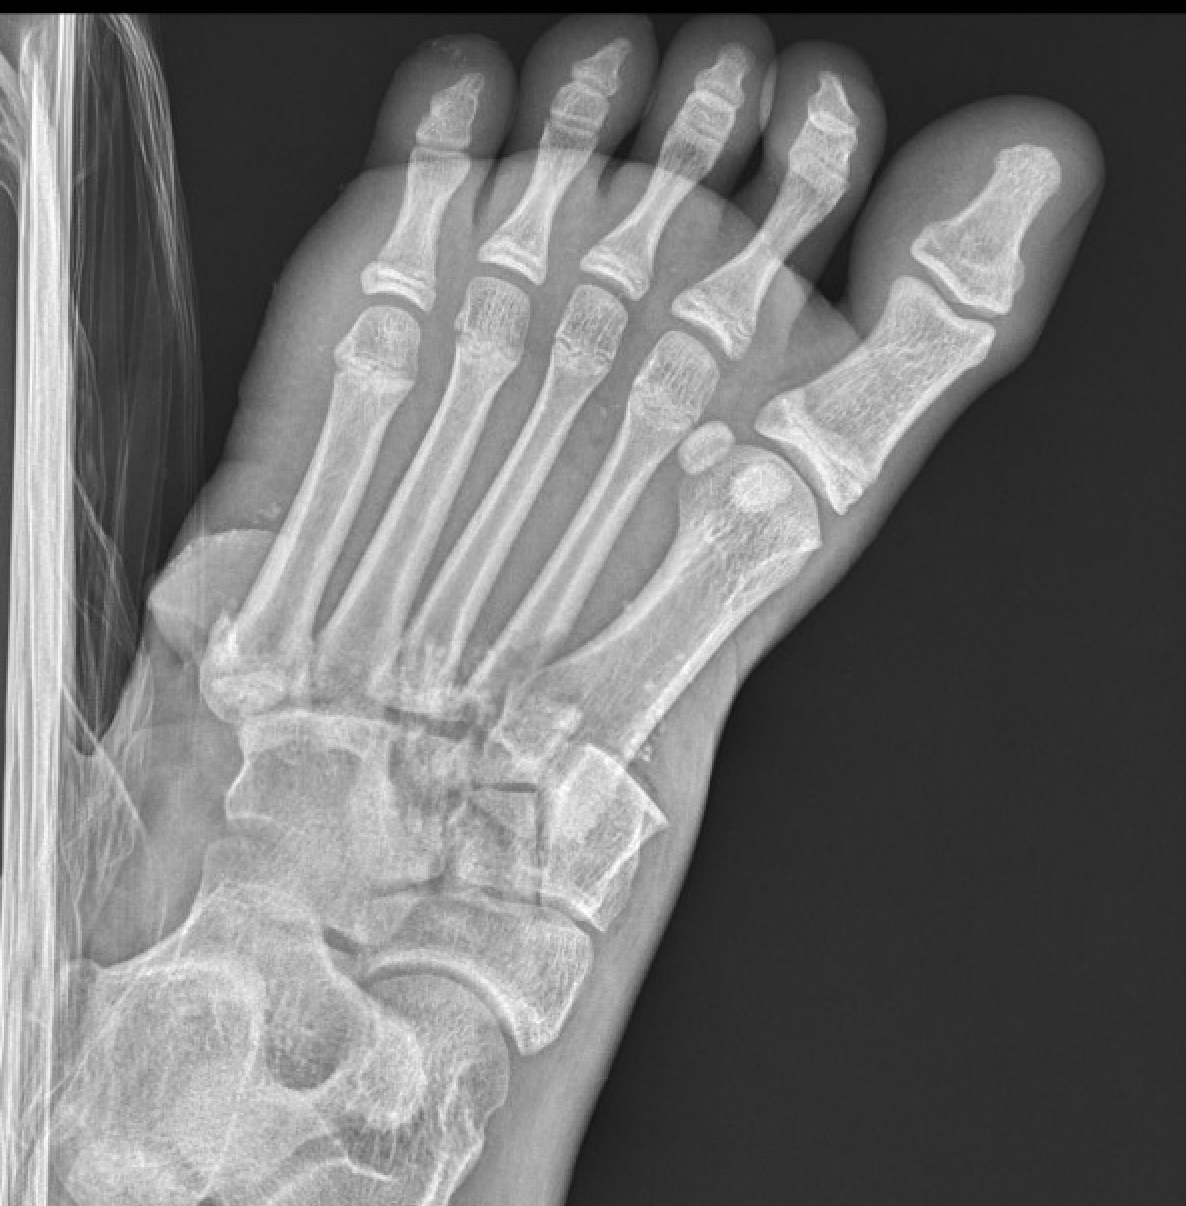

| Isolated | Homolateral | Divergent |

|---|---|---|

| Only 1st MT injured / displaced | All 5 metatarsals displaced in same direction |

1st metatarsal displaces medially Other 4 metatarsals displace laterally |

| Most common | Least common | |

1. Diastasis of the intermetatarsal gap between the 1st and 2nd metatarsals

2. Widening of the space between the medial cuneiform and base of 2nd metatarsal

3. Second metatarsal Fleck sign - avulsion of Lisfranc ligament from base of 2nd metatarsal

4. Widening of inter-cuneiform distance

5. Dorsal subluxation of the metatarsals

6. Tarsometatarsal alignment disruption

- medial border 1st metatarsal aligns with medial border medial cuneirform (AP foot)

- medial border 2nd metatarsal aligns with medial border middle cuneiform (AP foot)

- medial border 3rd metatarsal aligns with medial border lateral cuneiform (AP view)

- medial border 4th metatarsal aligns with medial border of the cuboid (oblique view)